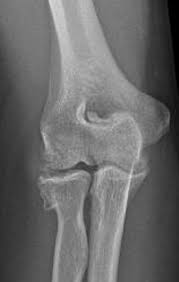

The common extensor tendon attaches to the lateral epicondyle, acting as the common attachment for the superficial extensor muscles of the forearm. The lateral epicondyle of the humerus is a large, tuberculated eminence, curved a little forward, and giving attachment to the radial collateral ligament of the elbow joint, and to a tendon common to the origin of the supinator and some of the extensor muscles. Tennis elbow assessment explore the. Related online courses on physioplus. Lateral epicondylitis is defined as a pathologic condition of the wrist extensor muscles at their origin on the lateral humeral epicondyle. This area can become tender to the touch. Pain is felt over the lateral epicondyle and radiates down forearm. Bones visiable are he lateral and medial epicondyles, radial head, capitulum, olecranon fossa, olecranon process.

Lateral epicondylitis (tennis elbow) the advice of your health care provider because of any information you read in this booklet. Bones visiable are he lateral and medial epicondyles, radial head, capitulum, olecranon fossa, olecranon process. Pain upon resisted wrist extension. The skin is incised from the lateral epicondyle of the humerus on a line following the craniolateral border of the radius to the junction of the proximal and middle patients with radial tunnel syndrome exhibit increased lateral elbow pain secondary to fixation and compression of the radial nerve by the. Resisted wrist extension with elbow fully extended.